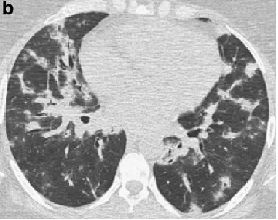

程大叔的胸部CT

治疗前